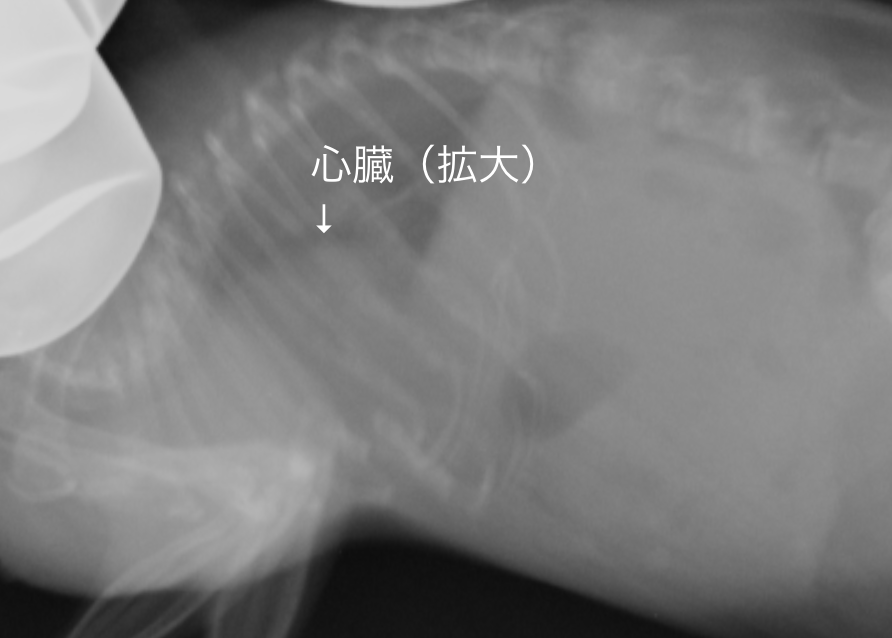

画像は心筋症ハムスターのレントゲン画像です。

心筋症の症例です。心臓が拡大しています

正常画像と比べ明らかに心臓が拡大しているのがわかります。また肺の領域も白く見え肺水腫もしくは胸水の存在が疑われます。